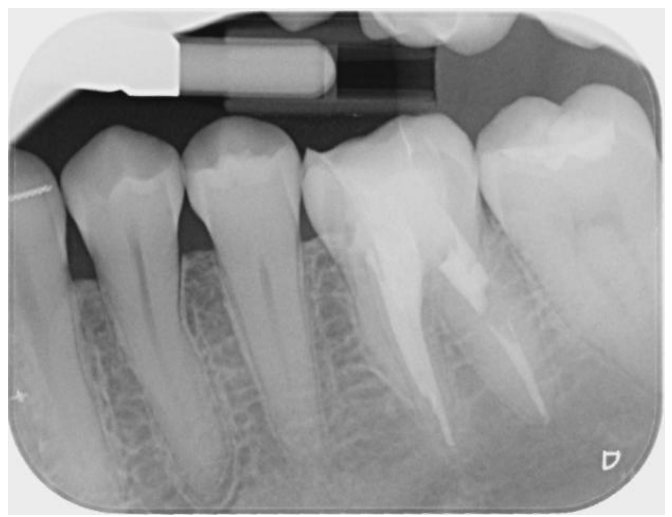

To assess the extent of the fracture and plan for removal, we obtained periapical radiographs and a cone-beam computed tomography (CBCT) scan. The imaging revealed the fractured NiTi instrument lodged deep within the canal system, complicating its retrieval due to its position approximately 8 mm beyond the apical foramen.

Fig 1, Fig 2, Fig 3, Fig 4, Fig 5, Fig 6, Fig 7

Figure 2

Figure 3